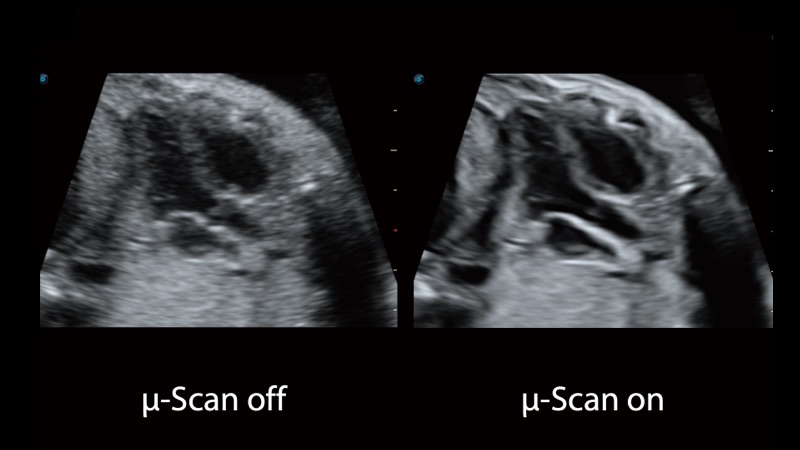

開立醫(yī)療通過不斷的技術(shù)創(chuàng)新,為大眾的生命健康提供持續(xù)關(guān)愛。P12 Plus采用全新一代超聲成像平臺(tái),新平臺(tái)旨在將真實(shí)還原組織解剖結(jié)構(gòu)作為首要目標(biāo)。平臺(tái)采用全新集成化硬件模塊,搭載新一代芯片,系統(tǒng)性能得到大幅提升,為您的診斷提供了豐富的臨床信息。優(yōu)異的圖像表現(xiàn),豐富的探頭配置,全面的應(yīng)用功能,為您日常診斷提供了可靠的助手。

P12 Plus

彩色多普勒超聲診斷系統(tǒng)